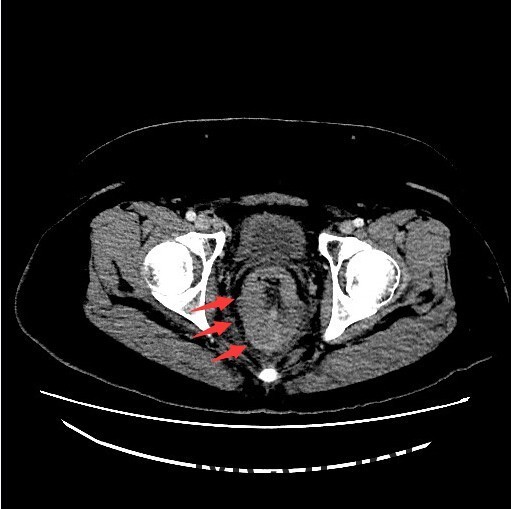

查体:肛查(KC位):肛周未见外痔,直肠指检可及环形多发内痔,部分质地较硬,有触痛,直肠壁可及多发结节,有触痛,指套退出有染血。 辅查:腹部CT示:直肠癌,累及肠壁全层,并周围肠系膜多发淋巴结转移,全身核素骨扫描结果提示:右侧坐骨轻度代谢活跃,建议定期复查以排除骨转移瘤可能,肿瘤标记物未见明显异常。肠镜示:1.直肠Ca?2.结肠息肉(已钳除)。

诊断:直肠癌? 治疗:入院后完善相关检查,肠镜活检病理示:B细胞源性非霍奇金淋巴瘤。肿瘤标记物未见明显异常。现患者要求暂缓手术治疗,办理出院。

讨论:胃肠道是原发性结外淋巴瘤最常见的累及部位。其中胃是最常见的发病部位,其次是小肠,而结肠和直肠少见。本例属于直肠淋巴瘤,属于少见肿瘤,影像表现与直肠癌相似,因此临床常常误诊为直肠癌,本例即误诊为直肠癌。影像学上只要认真观察一般能通过以下几点将两者鉴别开:淋巴瘤一般累及的肠段较长,肠壁较厚,肠腔变窄不明显,呈动脉瘤样扩张,没有肠梗阻表现,周围脂肪界面清晰。而大肠癌则相对较局限,常伴有肠腔的狭窄及肠梗阻的表现,而且常通过浆膜直接向周围浸润,周围脂肪间隙模糊。只要认真寻找这些影像征象,还是能够将两者较好的区别开来。